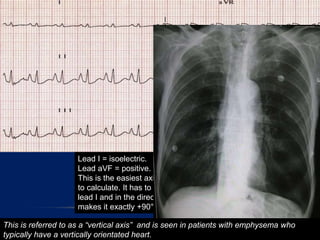

Lead I = isoelectric.

Lead aVF = positive.

This is the easiest axis you will ever have

to calculate. It has to be at right angles to

lead I and in the direction of aVF, which

makes it exactly +90ยฐ!

This is referred to as a โ€œvertical axisโ€ and is seen in patients with emphysema who

typically have a vertically orientated heart.